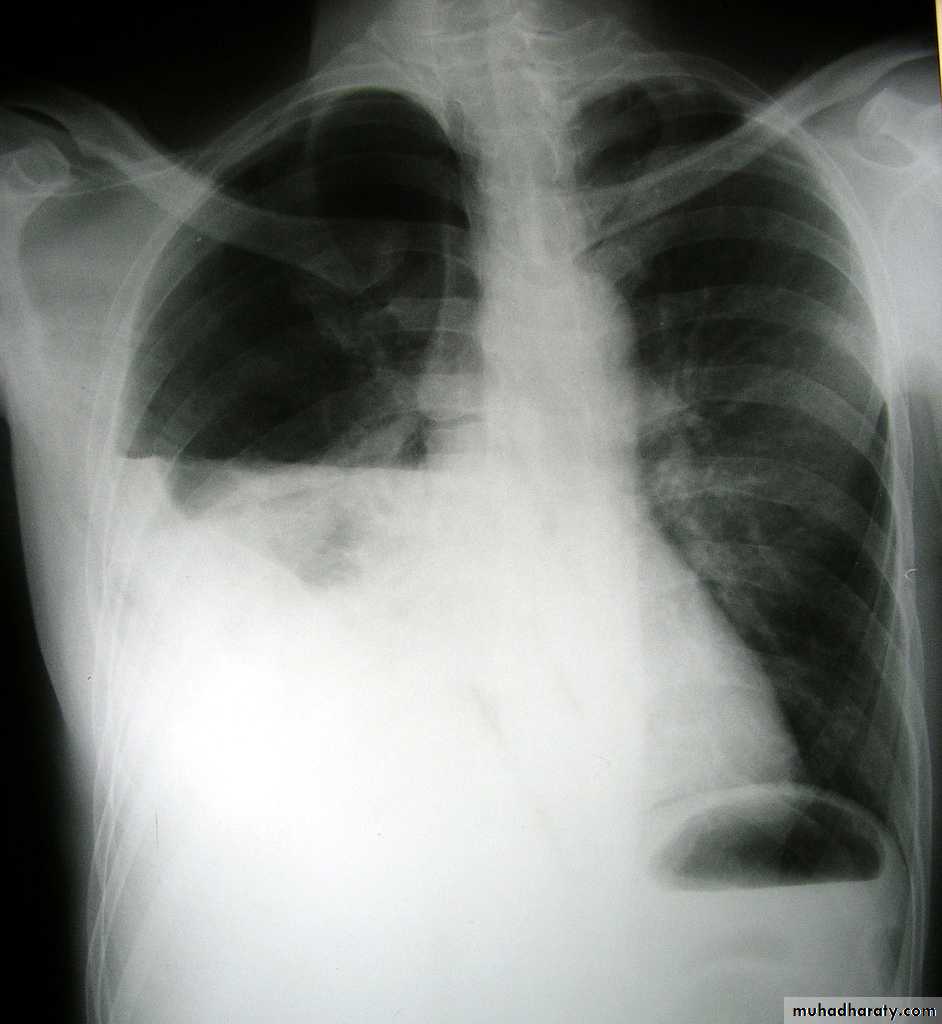

PneumothoraxX-ray pneumothorax

X-ray pneumothorax

X-ray tension pneumothorax